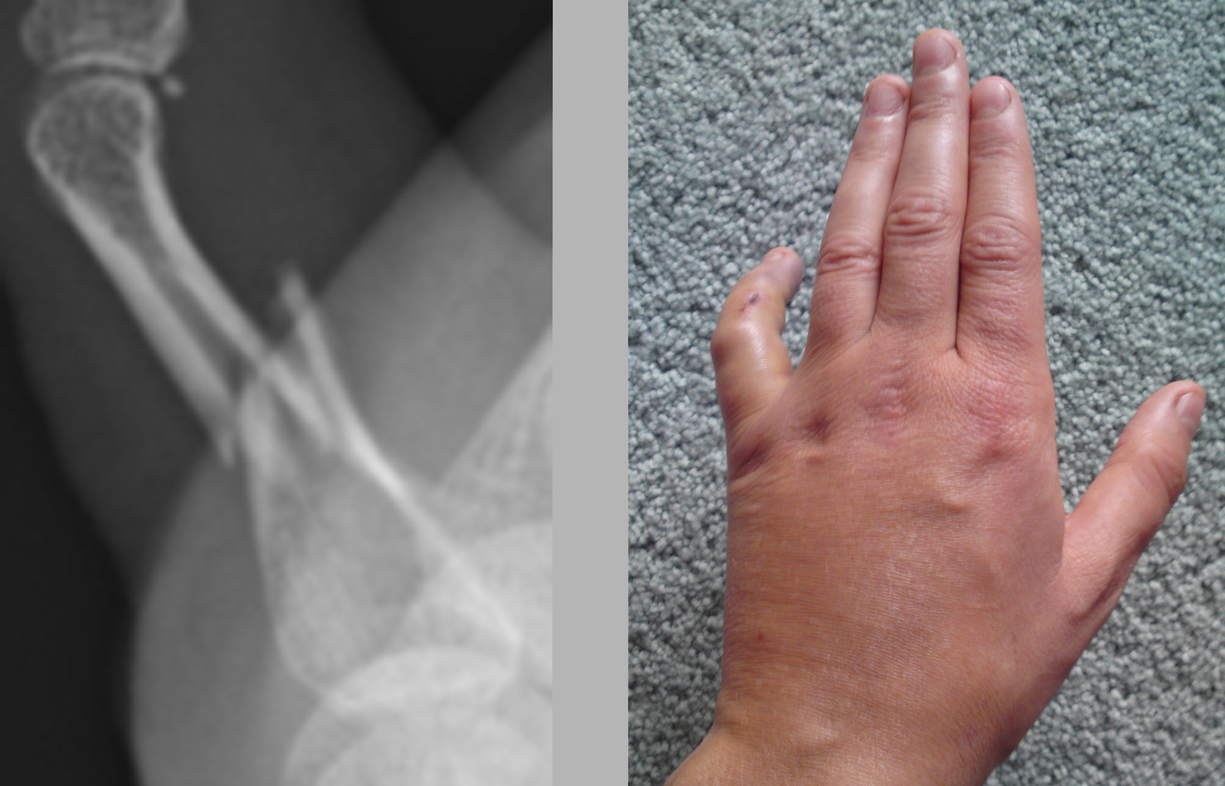

When my arm was in plaster I initially found that the plaster felt supporting because it restricted movement which had been painful. It took over the job on the outside that the bone would have done on the inside, forming an exoskeleton, and by doing so gave the bone the opportunity to heal itself. By the second week the pain had died down and I wanted to be able to move my wrist and thumb but couldn’t. As well as being supported I now felt contained in the plaster; restricted and uncomfortable. After six weeks of not moving my hand it began to ache and I really felt the restriction of not being able to clench my fist. The bones in the hand move in so many directions all of which had been immobilised in the plaster except wiggling my fingers to keep circulation. When the plaster was taken off after nine weeks my hand was rigid and completely immobile, my wrist was locked solid and all my muscles had completely wasted away leaving a bony, shrivelled, scaly, distorted object. I had been looking forward to being able to move it again but the combination of being so stiff and feeling so fragile meant that much of the restriction remained even after the plaster was removed.

Whether the cast on my arm felt supportive or restricting was dependant on the condition of the arm. When the wrist was most injured and needed support then it was a positive experience. Once healed well enough the plaster served as protection from knocks for the new soft bone but also became restrictive. Whilst the plaster supports the bones it also causes the muscle to waste and this creates a conflict between doctors and physiotherapists. The doctor is concerned with the bone rather than the movement and so can be tempted to leave the plaster on too long causing irreversible damage to movement. There is a fine line between providing support and causing damage through restriction. What I find interesting in the tension between the physiotherapist and doctors is that the latter seeks to secure a static structure in repairing the bone whereas the physiotherapist’s purpose is to help restore movement in freeing the joints and rebuilding muscle.